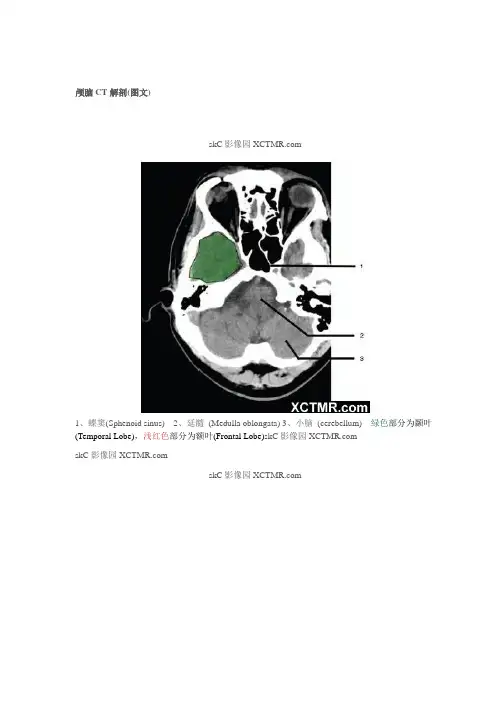

颅脑CT解剖(图文)skC影像园1、蝶窦(Sphenoid sinus)2、延髓(Medulla oblongata)3、小脑(cerebellum) 绿色部分为颞叶(Temporal Lobe),浅红色部分为额叶(Frontal Lobe)skC影像园skC影像园skC影像园4、第四脑室(Fourth ventricle)5、小脑中角(Middle cerebellar peduncle)6、乙状窦(Sigmoid sinus)7、颞骨及乳突气房(Petrous temporal bone and mastoid air cells)8、桥小脑角(Cerebellopontine angle)9、脑桥(Pons) 10、垂体窝(Pituitary fossa) 绿色部分为颞叶(Temporal Lobe),浅红色部分为额叶(Frontal Lobe)skC影像园skC影像园11、小脑蚓部(Cerebellar vermis) 12、基底动脉(Basilar artery) 13、桥前池(Prepontine cistern) 14、鞍背(Dorsum sellae) 15、侧脑室颞角(Temporal horn of lateral ventricle) 绿色部分为颞叶(Temporal Lobe),浅红色部分为额叶(Frontal Lobe)skC影像园skC影像园16、环池(Ambient cistern) 17、角间池(Interpeduncular cistern) 18、大脑角(Cerebral peduncle) 19、侧裂池(Sylvian fissure) 绿色部分为颞叶(Temporal Lobe),浅红色部分为额叶(Frontal Lobe) skC影像园skC影像园20、小脑上池(Third ventricle) 21、侧脑室前角(Frontal horn of lateral ventricle) 21a、第三脑室(Third ventricle) 绿色部分为颞叶(Temporal Lobe),浅红色部分为额叶(Frontal Lobe),黄色部分为枕叶(Occipital Lobe)skC影像园skC影像园22、尾状核头部(Head of caudate nucleus) 23、岛叶(Insular cortex) 24、外囊(External capsule) 25、豆状核(Lentiform nucleus) 26、丘脑(Thalamus) 绿色部分为颞叶(Temporal Lobe),浅红色部分为额叶(Frontal Lobe),黄色部分为枕叶(Occipital Lobe)skC影像园skC影像园27、纵裂(Interhemispheric fissure) 28、内囊前肢(Anterior limb of internal capsule)29、内囊膝部(Genu of internal capsule) 30、内囊后肢(Posterior limb of internal capsule) 31、侧脑室三角区及脉络丛钙化(Trigone of lateral ventricle and calcified choroid plexus) 32、侧脑室枕角(Occipital horn of lateral ventricle) 绿色部分为颞叶(Temporal Lobe),浅红色部分为额叶(Frontal Lobe),黄色部分为枕叶(Occipital Lobe),褐色部分为顶叶(Parietal Lobe)skC影像园skC影像园33、侧脑室体部(Body of lateral ventricle) 34、放射冠(Corona radiata) 浅红色部分为额叶(Frontal Lobe),黄色部分为枕叶(Occipital Lobe),褐色部分为顶叶(Parietal Lobe)skC影像园skC影像园35、半卵圆中心(Centrum semiovale) 浅红色部分为额叶(Frontal Lobe),黄色部分为枕叶(Occipital Lobe),褐色部分为顶叶(Parietal Lobe) 额骨(FB— Frontal bone) 顶骨(PB — Parietal bone) 枕骨(OB— Occipital bone)skC影像园skC影像园36、中央前回(Pre-central gyrus) 37、中央沟(Central sulcus ) 38、中央后回(Post-central gyrus) 浅红色部分为额叶(Frontal Lobe),褐色部分为顶叶(Parietal Lobe)skC影像园skC影像园 浅红色部分为额叶(Frontal Lobe),褐色部分为顶叶(Parietal Lobe)skC影像园skC影像园浅红色部分为额叶(Frontal Lobe),褐色部分为顶叶(Parietal Lobe)skC影像园。